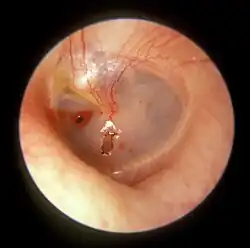

Surgical puncture for treatment of middle ear infections

In some cases, the pressure of fluid in an infected middle ear is great enough to cause the eardrum to rupture naturally. Usually, this consists of a small hole (perforation), from which fluid can drain out of the middle ear. If this does not occur naturally, a myringotomy (tympanotomy, tympanostomy) can be performed. A myringotomy is a surgical procedure in which a tiny incision is created in the eardrum to relieve pressure caused by excessive buildup of fluid, or to drain pus from the middle ear. The fluid or pus comes from a middle ear infection (otitis media), which is a common problem in children. A tympanostomy tube is inserted into the eardrum to keep the middle ear aerated for a prolonged time and to prevent reaccumulation of fluid. Without the insertion of a tube, the incision usually heals spontaneously in two to three weeks. Depending on the type, the tube is either naturally extruded in 6 to 12 months or removed during a minor procedure.[16]

Those requiring myringotomy usually have an obstructed or dysfunctional Eustachian tube that is unable to perform drainage or ventilation in its usual fashion. Before the invention of antibiotics, myringotomy without tube placement was also used as a major treatment of severe acute otitis media.[16]